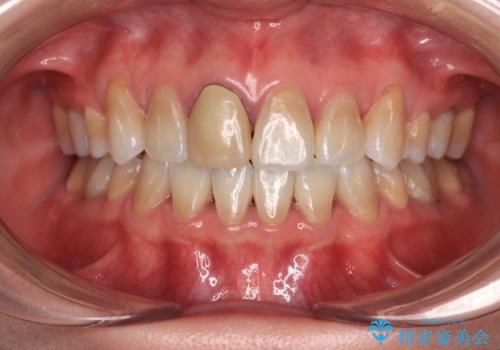

- 結婚式を前に、保険診療での前歯のクラウンが気になるとのことで来院された患者様です。

色合いだけでなく、歯肉の縁が黒くなっていることが分かります。

速やかに仮歯に交換し、オールセラミッククラウンにて補綴することとしました。